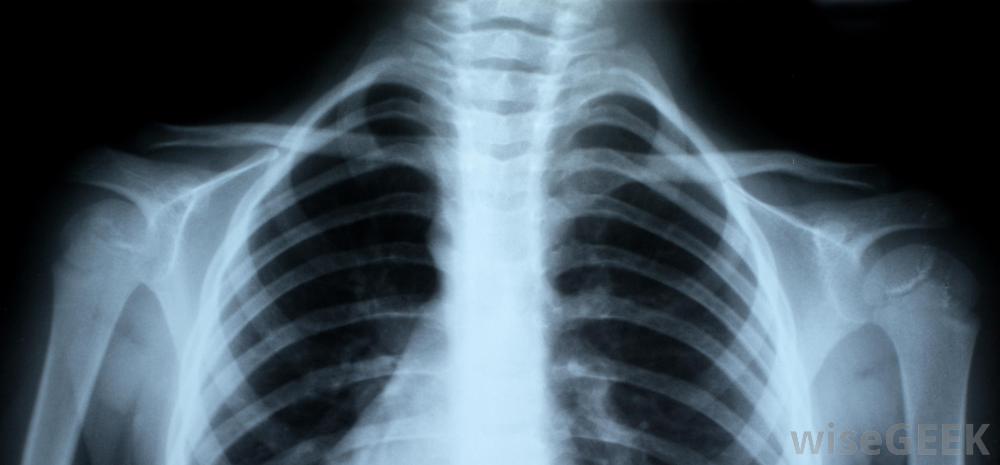

鎖骨,也稱鎖骨,是人體最常見的骨折之一。運動員,兒童,甚至嬰兒從產道出來都會經歷骨折。治療骨折的鎖骨通常不需要手術,但患者可以采取一些措施來妥善治療。為了治療骨折的鎖骨,患者應該去看醫生以確定是否有骨折。固定手臂、使用冷敷和服用止痛藥是治療的常見部分,一旦疼痛消退,進行一系列的運動訓練也可能是必要的人的骨架,包括紅色的鎖骨。如果一個人覺得自己的鎖骨斷了,在去看醫生之前,他應該盡量保持手臂不動。有時,骨折會導致開放性骨折,也就是說,當骨頭穿過皮膚時。如果骨折處有傷口,可能意味著骨頭打破了皮膚,但在患者移動時又重新進入。在這種情況下,患者應就醫,因為手術可能是清理傷口和防止感染的必要手段。射線照片可以向醫生顯示鎖骨是否斷裂鎖骨骨折愈合的時間長短取決于患者的年齡兒童通常在三到四周后痊愈。青少年可能在六到八周后痊愈,但是一個成年人可能要等四個月。一條吊帶或八字形繃帶可能要一直戴著。許多醫生更喜歡吊帶而不是繃帶,因為一個人戴著八字形繃帶時不可能正確地清洗,而且繃帶會比繃帶更不舒服,會引起更多的皮膚刺激。對于鎖骨骨折的病人,可能會開出或推薦不同形式的止痛藥,冷敷20分鐘左右建議每兩小時進行一次,以幫助減輕疼痛和減輕腫脹。疼痛消退后,最好開始移動手臂、手腕和肩膀,以防止其僵硬。醫生或理療師可以教患者進行可以保持手臂的鍛煉活動。在斷開的鎖骨完全愈合之前,不應嘗試運動和其他力量鍛煉。有時手術是治療鎖骨骨折的最佳選擇。這通常發生在開放性骨折或者如果骨頭沒有愈合。在手術過程中,醫生可能需要植入鋼板或螺絲釘。手術也可能是清理傷口和防止感染的必要手段。然而,鎖骨骨折的手術并不常見,而且骨頭通常在沒有任何干預的情況下愈合使用冷敷和止痛藥可以緩解鎖骨骨折帶來的不適。